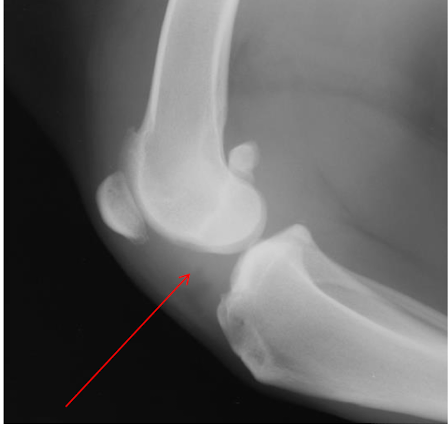

What is the arrow pointing to?

intra-capsular swelling